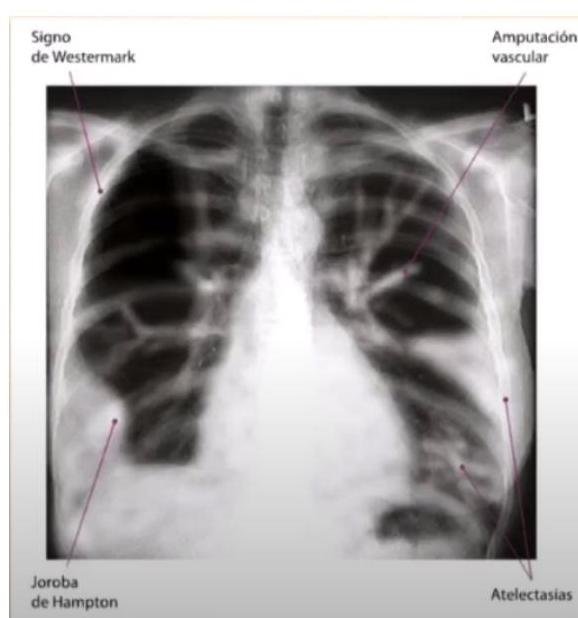

# ENFERMEDAD TROMOEMBÓLICA ## DEFINICIÓN El término trombosis se refiere a la formación de una masa anormal dentro del sistema vascular a partir de los componentes sanguíneos. La Enfermedad Tromboembólica Venosa (ETV) comprende un espectro de enfermedades que engloban la Trombosis Venosa Profunda (TVP) y de la Tromboembolia Pulmonar (TEP), ambos comparten los mismos factores predisponentes. La TVP es una oclusión de los vasos pulmonares debido a un coágulo sanguíneo, el 95% de los casos en el sistema venosos profundo de los miembros inferiores y posteriormente el émbolo se depoista en el área pulmonar. Cuando una TVP proximal no es tratada, ocurre una TP en el 33% de los casos y otro 33% presenta un embolismo subclínico. Otros orignees de émbolos son las venas pélvicas, las extremidades superiores y las cavidades cardíacas derechas.  # FISIOPATOLOGÍA El proceso de trombosis involucra diversos factores que predisponen a un individuo a sufrir de una oclusión trombótica que fueron descritos por Virchow desde el siglo XIX. ## TRÍADA DE VIRCHOW: - Lesión endotelial (Trauma, cirugía, fractura reciete, enveto previo de TVP) - Estasis o alteración del flujo sanguíneo (inmovilidad, obesidad, ICC, aumento PVC) - Estado hipercoagulable de la sangre (embaraza, postparto, ACO, cáncer, quemaduras severas) ## Triada de Virchow  Durante el episodio agudo se pueden apreciar las siguientes alteraciones fisiopatológicas: 1. Alteración del intercambio gaseoso: AUMENTO DEL ESPACIO MUERTO FISIOLÓGICO (zona que está siendo ventilada, pero no perfundida) por desequilibrio V/Q en el pulmón no obstruido (más perfusión que ventilación) y por shunt derecha a izquierda, que puede ocurrir a nivel intrapulmonar o intracardiaco. 2. Hiperventilación alveolar por estímulo refeljo nervioso. 3. Aumento de la resistencia dal flujo aérero por broncoconstricción de las vías aéreas distales al bronquio obstruido. 4. Disminución de la distensibilidad pulmonar por edema, hemorragia o pérdida de surfactante. 5. Aumento de la resistencia vascular pulmonar por obstrucción vascular o liberación de agnetes neurohumorales como la serotonina por las plaquetas. 6. Disfunción ventricular derecha. El fracaso ventricular derecho es la causa de muerte más habitual de la TEP. A medida que aumenta la resistencia vascular pulmonar, aumenta la tensión del VD, maor dilatación y disfunción ventricular. # EPIDEMIOLOGÍA - La ETV está ubicada en el 3o lugar como causa de muerte cardiovascular (después de enfermedad coronaria e isquemia cerebral) - Es un trastorno multifactorial, con incidencia anual de 1-2 por cada 1,000 personas - Más frecuente en hombres - Asociada a edad con incremento a 1 por cada 100 personas en mayores de 55 años. - Un 20 % de quien padece ETV no tiene factores de riesgo asociados. FACTORES DE RIESGO | RIESGO | ANTECEDENTE | | :--: | :--: | | ALTO | Fractura de cadera o miembros inferiores Cirugía ORTOPÉDICA Prótesis de cadera Cirugía mayor Poltirauma IAM Lesión de médula espinal | | MODERADO | Artroscopía Cateter central Quimioterapia Insuficiencia cardiaca congestiva Tratamiento hormonal Embarazo Trombofilia | | BAJO | Reposo en cama Inmovilidad Edad avanzada Laparoscopía Obesidad Venas varicosas Viajes en avión de largo recorrido Síndrome antifosfolípido Hiperhomocisteinemia Policitemia primaria EPOC | La resistencia a la proteína C activdada (Factor V de Leiden) es el estado de hipercoagulabilidad hereditario más frecuente en el TEP, seguido de las mutaciones del gen de la protrombina. Pero estos factores genéticos solo justifican 1/5 casos de TEP y la mayoría de los que tienen estos factores genéricos nunca desarrollan ETV. # CLÍNICA ## TVP DOLOR EN LA PANTORILLA: de inicio insidioso, que tiende a empeorar con el tiempo y se acompaña de palpación dolorosa - La TVP masiva es fácil de reconocer. El paciente presenta EDEMA DE MUSLO con palpación dolorosoa en zona inginal y sobre la vena femoral común. - La TVP de miembros superiores puede producir empastamiento de la fosa supraclavicular, aumento de diámetro del miembro o circulación colateral en la región anterior del tórax. ## TEP DISNEA: generalmente súbtia, es el síntoma más frecuente. Puede aparecer síncope o hipotensión brusca de causas no acalaradas. DOLOR PLEURÍTICO: aparece posterior a la disnea, siendo el segundo síntoma más frecuente. Taquicardia y Taquipnea: son signos constantes. Otros: hemoptsisis, opresión torácica, broncoespasmo | TEP Masivo | Se presenta con hipotensión o choque. Suele ser TEP de grana tamaño o difusos | | :--: | :-- | | TEP Moderado / Grande | Sin hipotensión ni choque Signos ecocardiográficos de sobrecarga de VD o elevación de marcadores de daño miocárdico | | TEP Moderado / Pequeño | Tensión arterial y función ventricular derecha normales. | # DIAGNÓTICO ## PROBABILIDAD CLÍNICA La estimación de la probabilidad clínica es el primer eslabón en la aproximación diagnóstica del TEP. El diagnóstico es difícil debido a lo inespecífico de la clínica. Lo primero que se debe hacer es terminar la probabilidad clínica, pues una probabilidad clínica baja de TVP o moderada/baja de TEP permiten descartar la enfermedad si el Dímero D es negativo sin utilizar otras pruebas de imagen. Dada la gravedad del proceso, un alto grado de sospecha clínica basta para iniciar anticoagulante. ## SISTEMA DE WELLS DE PROBABILIDAD CLÍNICA | Síntomas o signos de Trombosis Profunda | 3 | | :-- | :-- | | Diagnóstico alternativo menos probable | 3 | | FC >100 lpm | 1.5 | | Cirugía o inmovilización en las 4 semanas previas | 1.5 | | Episodio de tromboembolismo pulmonar o trombosis profunda previa | 1.5 | | Hemoptisis | 1 | | Cáncer | 1 | | PROBABILIDAD BAJA | 0-1 punto | | :--: | :--: | | PROBABILIDAD INTERMEDIA | 2-6 puntos | | PROBABILIDAD ALTA | >7 puntos | ## RADIOGRAFÍA Una placa normal o con escasas alteraciones aumenta la sospecha de TEP, aunque lo habitual es que existan anomalías: - Elevación del hemidiafragma - Atelectasias - Anomalías parenquimatosas pulmonares - Derrame pleural escaso y serohemático. SIGNO DE WESTERMARK: Oligohemia focal que produce hipertensión pulmonar. JOROBA DE HAMPTON: condensación parenquimatosa triangular de base pleural Asociado a TEP con infarto y presenta derra pleural de pequeña cuantía.  # ELECTROCARDIOGRAMA Las atleraciones más comunes - Taquicardia Sinusal y Anomalías Inespecíficas en el ST-T de V1 - V4. Puede haber signos de sobrecarga derecha como patrón SI,QIII,TIII (S en la derivación I, Q y T invertida en la II) ## LABORATORIO Marcadores Cardiacos: La elevación de Troponinas aumenta el riesgo de complicaciones y mortalidad en TEP estables. Gasometría: existe hipoxemia y aumento de gradiente alveoloarterial - Puede haber pacientes sin antecedentes de patología pulmonar con PO2 y D(a-a)O2 normales - La PaCO2 suele estar baja (hipoventilación refleja) - ALCALOSIS RESPIRATORIA. ## DÍMERO D Sensibilidad del 95% (85%-99%) y especificidad del 50% (29-71%) y un valor predictivo negativo del 95 al 100 %. Son generados por la acción del Factor VIII de coagulación sobre los monómeros y multímeros de fibrina Su elevación revela la presencia de fibrinólisis endógena, pero no es específico de TEP. Aumenta también en: IAM, neumonía, fallo derecho, carcinomas, cirugía, inmovilizaciones. Se debe determinar mediante ELISA Tiene un elevado valor predictivo negativo, especialmente si se combina con la probablidad clínca del Sistema Wells - Probabilidad Baja/Intermedia y Dímero D <500 \rightarrow se descarta TEP. No es muy util en pacientes con cáncer o cirugía reciente ya que la mayoría tiene >500 ng / ml ## TAC ESPIRAL CON CONTRASTE ## 1ra elección: ante la sospecha de TEP - Tiene sensibilidad mayor del 80 % y una especificdad mayor del 90 %. - Visualiza arterias del sexto orden - Tiene contraindicación la IR o alergia al contraste. Si el resultado es normal y la sospecha clínica es alta - ANGIOGRAFÍA PULMONAR. ## ANGIOGRAFÍA PULMONAR - Era el GOLD STANDARD hasta antes de la APTC. - Puede precisarse para el diagnóstico cuando hay una alta sospecha clínica y los otros estudios (TC Espiral, Ecografía) son negativos. - Se debe realizar en pacientes que se vayan a someter a algun tipo de intervención como una embolectomía o una trombolisis dirigida por cateter. # ANGIOGRAFÍA POR TOMOGRAFÍA La APTC Es la prueba que actualmente se considera GOLD ESTÁNDAR al ser menos invasiva. ## GAMMAGRAFÍA DE PERFUSIÓN PULMONAR  - Prueba de segunda línea, indicada en casos en los que no se pueda realizar la Tomografía. - Un resultado normal excluye el diagnóstico de TEP. - Un resultado anormal, se debe combinar con el de la gammagrafía de ventilación y así determinar la probabilidad gammagráfica de TEP.. - Una gammagrafía de alta probabilidad diagnóstia es la que presenta 2 o más defectos de perfusión segmentarios con gammagrafía de ventilación y radiografía de tórax normales. ## ECOCARDIOGRAFÍA - Baja sensibilidad para detectar TEP, puede ser util en casos de sospecha de TEP clínicamente graves, puesto que valora la función ventricular derecha y visualiza trombos importantes. - Se realiza transesofágico o transtorácico. ## ECOGRAFÍA VENOSA - Es la prueba no invasiva más utilizada en la actualidad para valorar TVP y ha llevado al desuso a la plestimografía y a la flebografía isotópica. - Es fiable en sintomáticos ambualtorios con sospecha de TVP; en sintomáticos y hospitalizados, pero la tasa de detección de TVP es mucho más baja. | TROMBO NO MASIVO | Presenta un excelente pronóstico y es la más frecuente. | | :--: | :-- | | TROMBO SUB-MASIVO | Presenta disfunción del ventrículo derecho del corazón pero con una presión arterial normal | | TROMBO MASIVO | Afectación de al menos la mitad de los vasos del pulmón. | # TRATAMIENTO El tratamiento primario consiste en la disolución del coágulo, ya sea mediante trombolisis o mediante embolectomía. La anticoagulación o el filtro de vena cava constituyen más bien una prevención secundaria a un nuevo episodio. - El tratamiento anticogulante es el factor más importante en la terpéutica de ETV. ## HEPARINAS ## HEPARINA NO FRACCIONADA (HNF) - Acelera la acción de la antitrombina III e inactiva el factora Xa, por lo que se previene la formación de un trombo adicional y permite que la fibrinolisis endógena disuelva algo del émbolo. - Requiere monitorizar TTPa, que debe duplicarse. - Su acción puede ser revertida con SULFATO DE PROTAMINA. - Se utiliza fundamentalmente en TEP con compromiso hemodinámico junto a los fibrinolíticos. ## HEPARINA DE BAJO PESO PESO MOLECULAR (HBPM) - Se administra por vía subcutánea. - Tiene una vida media plasmática más larga, ya que interactúa menos con las plaquetas y las proteínas. - Apenas se unen la antitrombina III y ejerce sy efecto fundamentalmente inactivando el factor Xa. - La monitorización del TTPa y el ajuste de dosis no suele ser necesaira, salvo en casos de obesidad, embarazo o IR grave. - En situaciones hemodinámicamente estables es tan eficaz y segura como la HNF. ## FONDOPARONUX Es un inhibidor selectivo del factor Xa que se administra por vía subcutánea una sola vez al día.no necesita controles de coagulación pero debe reducirse su dosis en IR. # ANTICOAGULANTES ORALES Inhibien la activación de los factores de coagulación dependientes vitamina K (II, VII, IX y X) ## Fármaco más utilizado - WARFARINA - Se administra desde el día siguiente del inicio de la heparina y se mantiene simultáneamente durante al menos 5 días. - El mantenimiento requiere de un INR entre 2-3 - Si el paciente está hemodinámicamente estable y adecuada función del Ventrículo derecho, los anticoagulantes son suficientes para buenos resultado. CONTRAINDICADOS EN EL EMBARAZO por teratogenia de los cumarínicos. El acenocumarol junto con la HNF se inicia hasta después de I parto, independientemente de la heparina utilizada. ## TROMBOLÍTICOS 1ra elección en TEP MASIVO (única indicación aprobada) y en la TVP Iliofemoral masiva o de cava inferior. - Debe realizarse de forma precoz, aunque puede haber respuesta hasta 2 semanas tras el TEP. - Objetivo: rápida lisis del trombo, aocrtando la fase de alto riesgo y reduciendo la mortalidad. - Fármacos empleados: Urocinasa, Estreptocinasa, Activador Tisular del Plasminógeno (rTPA). ## TRATAMIENTO INVASIVO Colocación de filtros en la cava inferior, embolectomía (si hay compromiso hemodinámico grave que no responde a fibrinolíticos) o la tromboendareterectomía (en los casos de hipertensión pulmonar crónica secundaria a TEP con clínica grave) ## Indicaciones del filtro en cava inferior: - Contraindicaciones o complciaciones de anticoagulación en pacientes con ETV o alto riesgo de la misma. - TEP recurrente pese a anticoagulación - Gran trombo flotante en vena cava inferior - Realización simultánea de embolectomía o tromboendarterectomía - Profilaxis en riesgo extremo. Los fltros evitan TEP en la fase aguda pero a largo plazo aumentan el riesgo de TVP, por lo que los pacientes que lo usen, deben permanecer anticoagulados. ## DURACIÓN DE ANTICOAGUALNTES Se recomienda 3 - 6 meses cuando es el primer episodio en pacientes con factores de riesgo reversibles. En caso contrario, mantenerlo indefinidamente, valorando periodicamente si el riesgo de sangrado supera al beneficio de la anticoagulación.  # DIGNÓSTICO TEP  (c) Copyright 2021-2022 Joyas ENARM - Todos los derechos reservados -